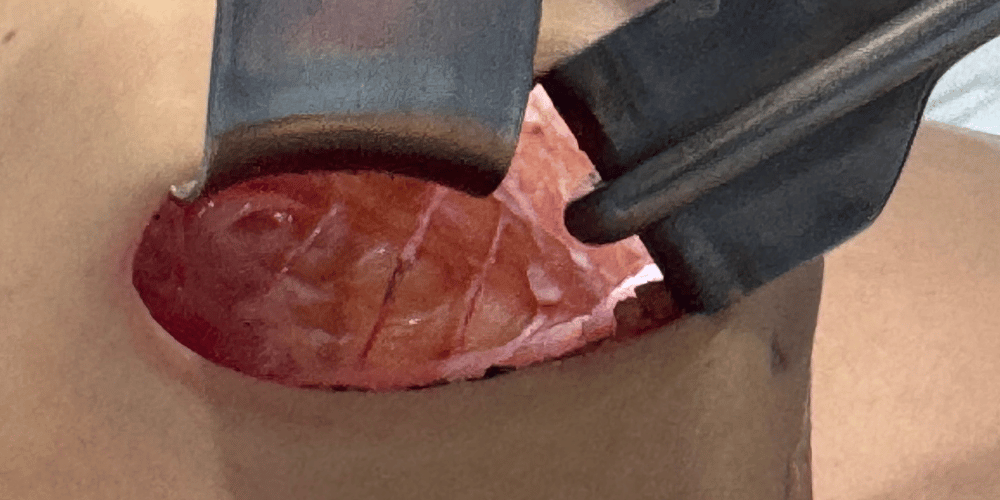

剥がす

アクアフィリングが体の中で被膜(膜)を作っている場合は、その皮膜を切除し、中のアクアフィリングを取り除きます。

プロセス:剥がす